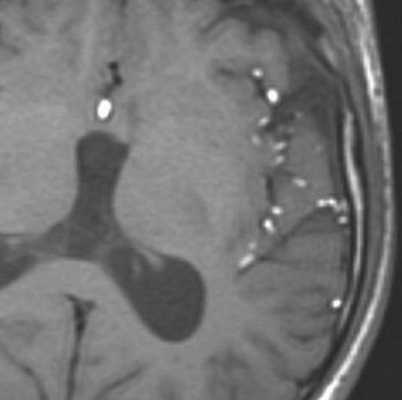

МРТ головного мозга. Т1-взвешенные корональная и сагиттальная МРТ. Эпидермоидная киста левой височной доли.

Дермоидные кисты встречаются реже эпидермоидных, составляя около 0,3 % от внутричерепных образований. Обычно выявляются в возрасте между 10 и 20 годами. Морфологически от эпидермоидов их отличает наличие эктодермальных элементов - волосяных фолликулов, потовых желёз и т.д. Типично они расположены по средней линии (в отличие от эпидермоидов, которые чаще внеосевые): в супраселлярной цистерне, субфронтально, вокруг моста и, очень редко парапинеально, периорбитально, в IV желудочке, в области конского хвоста и интрадиплоидно. От эпидермоидных кист на МРТ головного мозга их отличает только выраженная неоднородность структуры, кроме того, они всегда яркие на Т1-зависимых МРТ головного мозга за счёт большого содержания липидов. При разрыве и прорыве в субарахноидальное пространство в нём появляется уровень, на Т1-зависимых МРТ головного мозга светлый жир плавает на ликворе.

![Dermoid rupture]()

МРТ головного мозга. Т1-взвешенная аксиальная МРТ. Прорыв дермоидной кисты в субарахноидальное пространство.